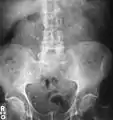

Calcium-containing stones are relatively radiodense, and they can often be detected by a traditional radiograph of the abdomen that includes the kidneys, ureters, and bladder (KUB film).[58] KUB radiograph, although useful in monitoring size of stone or passage of stone in stone formers, might not be useful in the acute setting due to low sensitivity.[59] Some 60% of all renal stones are radiopaque.[60][61] In general, calcium phosphate stones have the greatest density, followed by calcium oxalate and magnesium ammonium phosphate stones. Cystine calculi are only faintly radiodense, while uric acid stones are usually entirely radiolucent.[62]

Radiograph showing a large staghorn calculus involving the major calyces and renal pelvis in a person with severe scoliosis